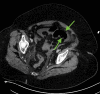

The prothrombotic nature of severe acute respiratory syndrome coronavirus 2 (SARS-CoV-2) has been well-established since the start of the global coronavirus disease 2019 (COVID-19) pandemic. Mesenteric artery thrombosis and acute mesenteric ischemia are, on their own, rare occurrences and often present with fatal gastrointestinal (GI) pathologies requiring quick identification and intervention by the clinician to improve clinical outcomes. SARS-CoV-2 infection can present with acute GI pathologies and warrants further investigation regarding anticoagulation therapy in COVID-19 positive patients. We report on a 64-year-old woman infected with SARS-CoV-2 who presented with superior mesenteric artery thrombosis and acute intestinal ischemia.